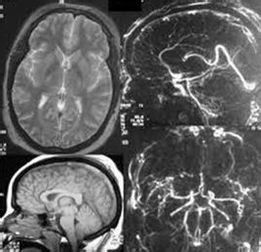

9 手術治療 急性顱內壓增高應做CT或MRI檢查確定血液、腦脊液和水腫組織的病理容積。手術治療方法包括切除顱內占位性病變、腦脊液引流和顱骨開瓣減壓手術。腦室引流對恢復腦脊液的正常循環具有重要意義,最簡單的手術是腦室持續引流,可直接放出腦脊液,使腦室縮小,達到降顱壓目的。要防止感染,避免引流管堵塞。腦室引流或腦脊液分流術是緩解嚴重顱內高壓症的重要手段。若發生腦疝可酌情行減壓術。要充分運用好去顱骨瓣減壓手術,在內科保守治療失敗的情況,不要忘記這是最好的降顱壓手段之一。